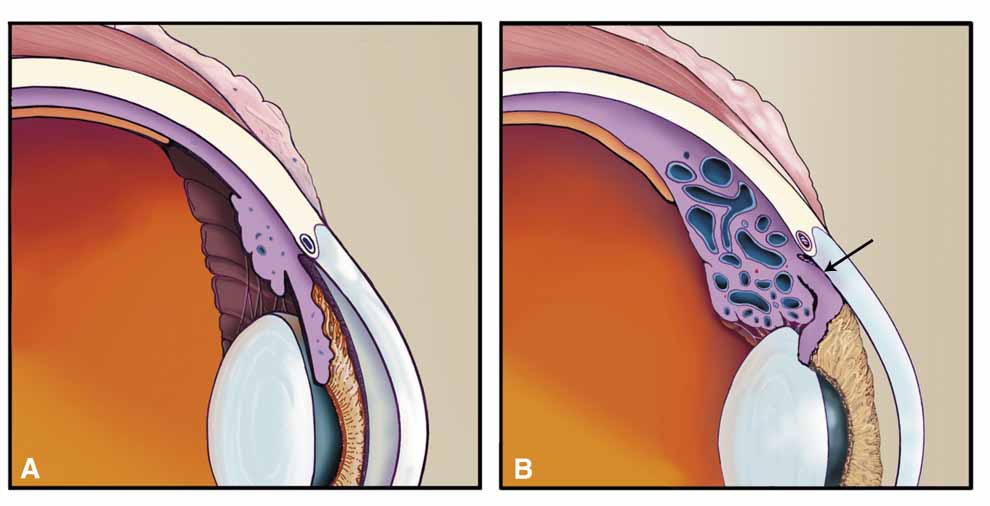

CYCLOCONGESTIVE/CILIOCHOROIDAL EFFUSION SYNDROME

All disorders in this group have some degree of choroidal congestion (Table 6), which may be noted by the usual clinical signs of clinical moundlike or annular choroidal detachment or be completely undetected, particularly if anteriorly placed and hidden behind the iris.82 Choroidal congestion can produce forward rotation of the ciliary body, resulting in closure of the peripheral angle and a shallow but preserved central anterior chamber (Fig. 17).83 Although this may appear a contradiction of terms because choroidal detachments are usually associated with hypotony, experimental detachments of the ciliary body do not themselves result in aqueous shutdown,84 suggesting that low pressure with choroidal effusion is due to hyposecretion secondary to concurrent iridocyclitis. Continued aqueous production in the presence of a closed peripheral angle results in an acute pressure elevation. Some clinical diseases sharing this mechanism have been mislabeled “malignant glaucoma,” an unfortunate name that adds mystique and confusion to the mechanism underlying these diseases. Though we prefer the term cyclocongestive to describe those disorders sharing this mechanism, other terms have been suggested including ciliochoroidal effusion syndrome.85 Either is descriptive of the pathophysiologic mechanisms that cause this clinical presentation. Miotics and peripheral iridectomy may worsen these conditions, whereas they are a first-line choice in the treatment of primary angle-closure glaucomas. Although cyclocongestive glaucoma may initially begin by ciliary body rotation with peripheral iris blocking the trabecular meshwork, if it is left untreated or diagnosed incorrectly, permanent, chronic angle closure may result, requiring goniosynechialysis or filtering surgery for adequate pressure control. Filtration surgery may actually precipitate the disorder in some cases.86

Fig. 17 A. Normal anatomy. B. Cyclocongestive glaucoma. Scleral buckling and other conditions may obstruct vortex venous outflow, resulting in choroidal congestion and detachment. Swelling of the ciliary body rotates this structure about the scleral spur, closing the peripheral angle. Note the loss of visible angle structures. Laser iris retraction is the treatment of choice in cases resistant to conservative therapy (cycloplegics, topical corticosteroids, timolol maleate, and acetazolamide).

Postoperative Scleral Buckling

Although postoperative pressure elevation following a routine scleral buckling is common, the incidence of clinically significant pressure elevations manifesting as pain and corneal edema is low.87 Choroidal congestion, which may be obvious or detectable only by ultrasonography, causes forward rotation of the ciliary body and closure of the peripheral angle. This situation is more likely to occur as a result of closure or compression of the vortex veins by broad scleral exoplants, which encourages postoperative choroidal edema.88 Exacerbating factors include excessive cryoretinopexy (choroidal congestion), drainage of subretinal fluid, and paracentesis during surgery.89 Treatment should include a trial of acetazolamide, atropine, corticosteroids, and aqueous suppressants. If no improvement is noted in 5 to 7 days, then peripheral laser iris retraction (laser iridoplasty = laser gonioplasty = iridoretraction) may thermally contract the iris, pull open the angle, and relieve the pressure elevation.90 If this fails, choroidal drainage combined with release of the scleral buckle will eliminate the mechanical obstruction of the vortex system.91